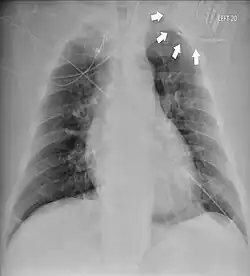

Das Twiddler-Syndrom ist eine seltene Komplikation nach dem Einbau eines Herzschrittmachers oder Defibrillators, bei der der Generator mit der Elektrodensonde (mehrfach) verdreht ist und die zur Funktionsstörung und Dislokation der Elektrode führt.[1][2]

Die Rotation des Herzschrittmachers kann zur Dislokation und Bruch der Defibrillatorelektrode führen. Die Folgen sind z. B.:

- Stimulation des Nervus phrenicus mit Zwerchfellzuckungen

- Stimulation des Plexus brachialis mit rhythmischen Armzuckungen